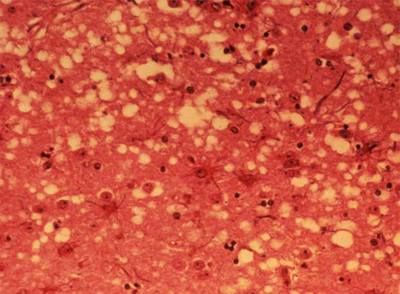

Creutzfeldt-Jakob pertenece a un grupo de enfermedades llamadas encefalopatías espongiformes transmisibles (EET) que dejan el cerebro con el aspecto de una esponja. "Es una enfermedad rara, con una incidencia de uno o dos casos por millón de habitantes y año. Se trata de una degeneración del sistema nervioso en la cual hay una sustitución de la proteína priónica normal por una proteína anormal que se llama prión. Pese a ser una enfermedad poco frecuente, no está olvidada. La investigación sobre alzhéimer corre en paralelo y aporta datos aplicables a la ECJ", asegura Isidro Ferrer, director del Instituto de Neuropatología del hospital universitario de Bellvitge.